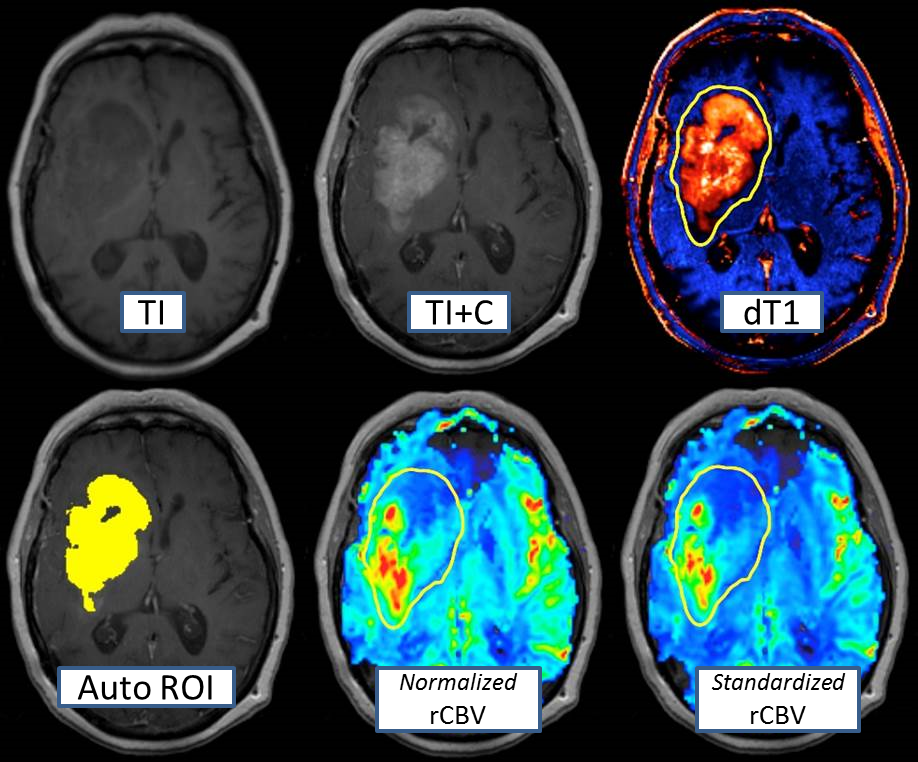

另外,此前2023年8月,GE医疗还与Imaging Biometrics公司签署合作协议。该公司开发了两款能够接受核磁共振(MRI)数据并自动计算定量和专有图像的应用程序:Neuro和Delta T1 maps。

图片

根据协议内容,这些应用程序将在GE医疗的MR Smart智选商城中订阅使用,并将直接提供给已经安装了GE医疗系统的站点以及计划安装的新系统。